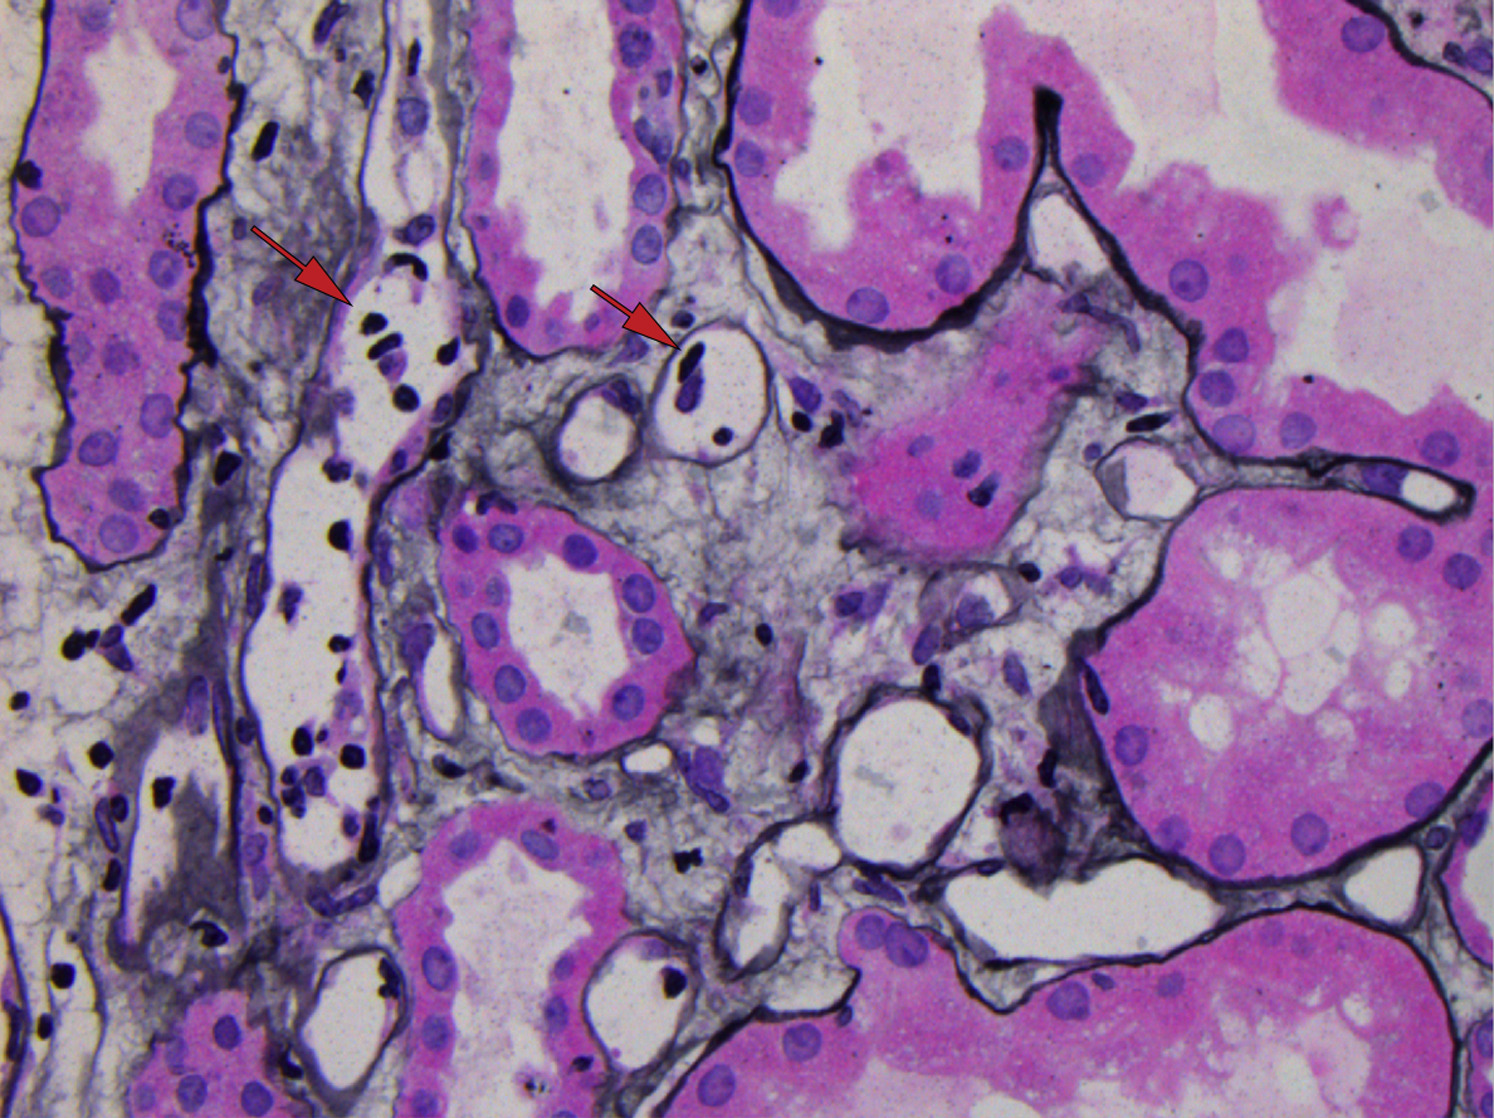

在过去几年中,我个人遇到的许多患者都与Rajora等人最近发表的AJKD in Practice文章中讨论的小插曲如出一辙。该患者患有丙型肝炎肝硬化、腹水和肝硬化[...]